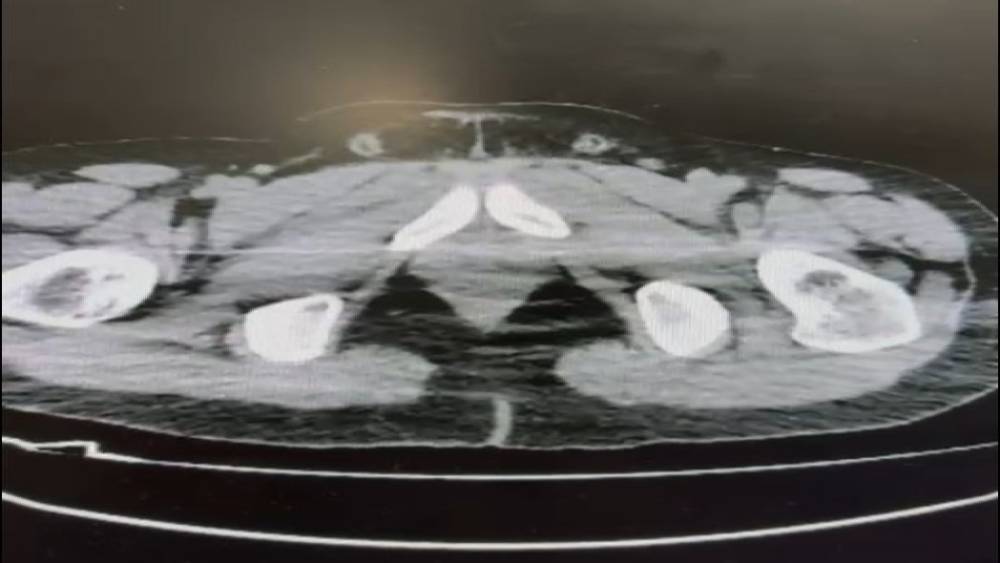

Nevşehir’de polis ekiplerince düzenlenen operasyonda midelerinde uyuşturucu sevkiyatı yapan 2 şüpheli gözaltına alındı.Nevşehir İl Emniyet Müdürlüğü Narkotik Suçlarla Mücadele Şube Müdürlüğü ekipleri, kentte uyuşturucu ve uyarıcı madde ticareti yapmak ve kullanmak suretiyle vatandaşları zehirleyen sokak satıcılarına yönelik çalışma başlattı. Cumhuriyet Başsavcılığı koordinesinde çalışmalarını yoğunlaştıran ekipler, şüpheliler S.B. ve O.R.’nin ’yutma yöntemi’ ile kente uyuşturucu madde sevk edeceği bilgisi üzerine operasyon düzenledi. Şüphelilerin ikametlerinde ve araçlarında yapılan aramada 101 kapsül halinde 722 gram uyuşturucu madde, 1 adet hassas terazi, uyuşturucu madde sevkiyatında yutma yönteminde kullanılan muhtelif materyaller, uyuşturucu madde ticaretinden elde edilen 20 bin 210 TL, bin 320 euro ve 10 ABD doları ele geçirildi. Emniyetteki işlemlerinin ardından adliyeye sevk edilen 2 şüpheli, çıkarıldıkları mahkemece tutuklanarak cezaevine gönderildi.

Nevşehir İl Emniyet Müdürlüğü Narkotik Suçlarla Mücadele Şube Müdürlüğü ekipleri, kentte uyuşturucu ve uyarıcı madde ticareti yapmak ve kullanmak suretiyle vatandaşları zehirleyen sokak satıcılarına yönelik çalışma başlattı. Cumhuriyet Başsavcılığı koordinesinde çalışmalarını yoğunlaştıran ekipler, şüpheliler S.B. ve O.R.’nin ’yutma yöntemi’ ile kente uyuşturucu madde sevk edeceği bilgisi üzerine operasyon düzenledi. Şüphelilerin ikametlerinde ve araçlarında yapılan aramada 101 kapsül halinde 722 gram uyuşturucu madde, 1 adet hassas terazi, uyuşturucu madde sevkiyatında yutma yönteminde kullanılan muhtelif materyaller, uyuşturucu madde ticaretinden elde edilen 20 bin 210 TL, bin 320 euro ve 10 ABD doları ele geçirildi. Emniyetteki işlemlerinin ardından adliyeye sevk edilen 2 şüpheli, çıkarıldıkları mahkemece tutuklanarak cezaevine gönderildi.